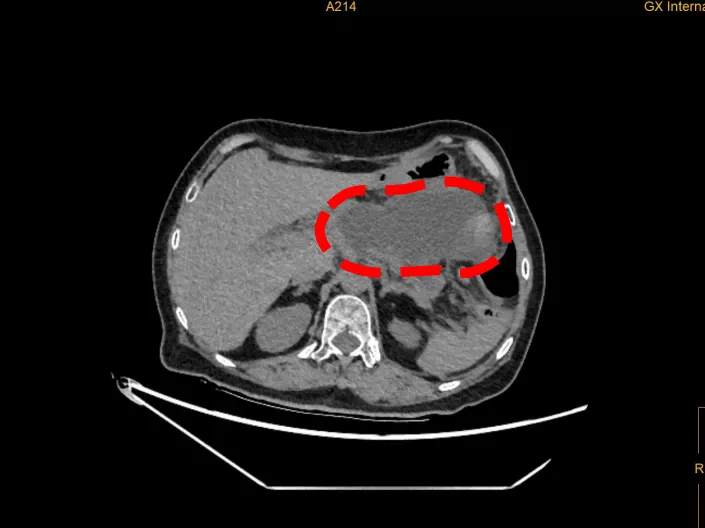

经CT检查发现,谭女士的囊肿已增大至154×90×75mm,大约为一个成年女性的两个拳头大小。唐国都表示,若继续增大,很有可能发生囊肿破裂,进而引发大出血、腹腔感染等危险状况。

谭女士体内一巨大的胰腺假性囊肿(红色部分)